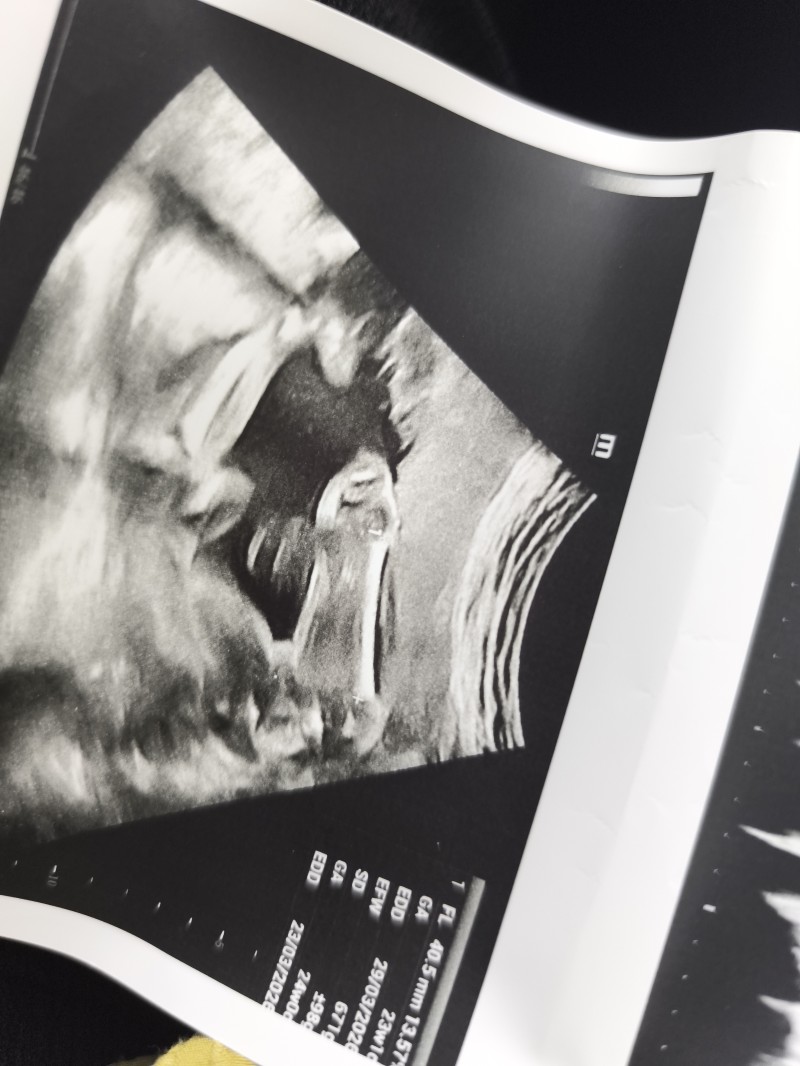

Bacak arasından tahmin yapar mısınız

Bir doktor kızlarda bacak arasında 3 cizgi oluyor demisti bence burada 3 cizgi yok erkek diye yorumluyorum

Neresinde 3 çizgi var bunun kız ben mi korum göremiyom bişey burda düz bacak goruyom cikintisiz

Iste ben de onu dedim yok cizgi :))

Bana kız gıbı geldi canm bacak arası boş ben bı çıkıntı gormedım çünkü

Erkek canım 3 çizgi oluyo kizlarda

Iki erkek cocuk annesi olarak ben kiz diyorum. Erkek olsa alttan cikinti baya belli oluyo bu haftalarda. Ben ikinci oglumu doktor daha soylemeden alttan goruntusunde anlamistim.